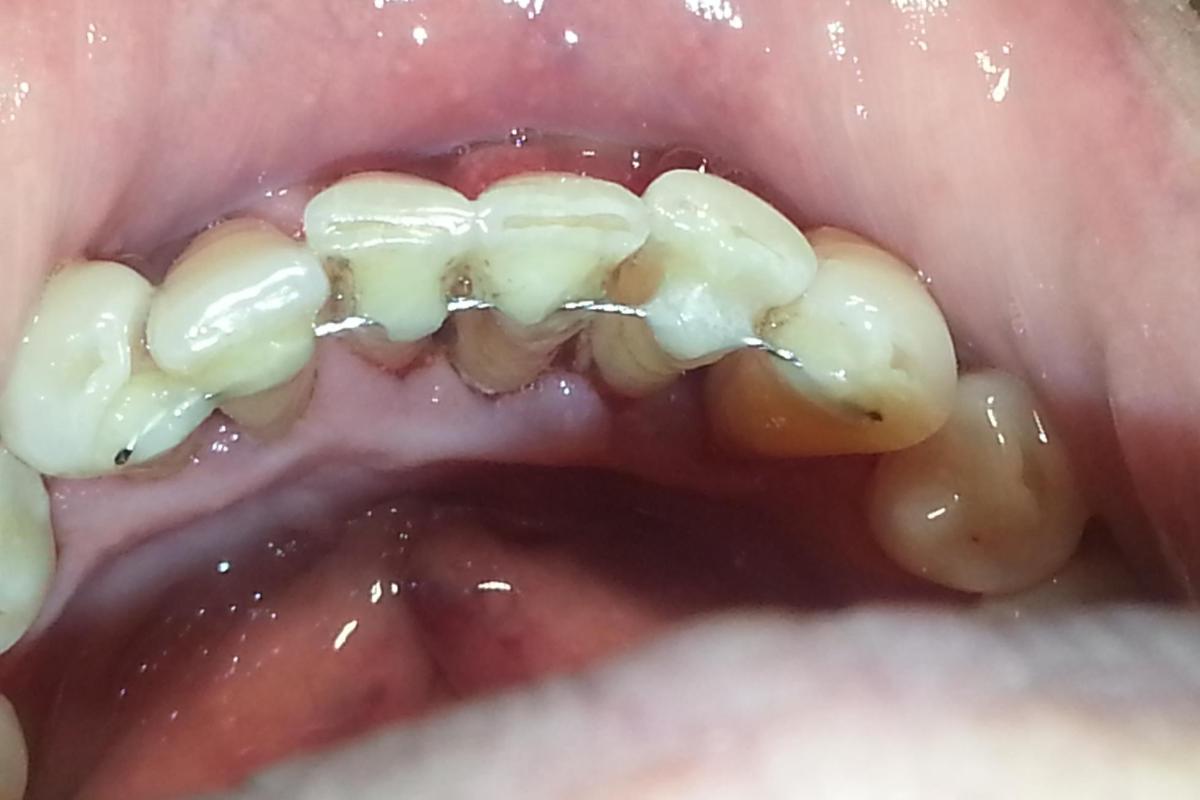

2. Внутрикорональное. Здесь металлическая дуга крепится на расшатывающиеся задние зубы (ряд моляров), часто не сбоку, а прямо на их поверхность. Таким образом, чтобы вставить туда шину, в эмали всех моляров проделывается небольшое отверстие и туда вставляется металлическая дуга.